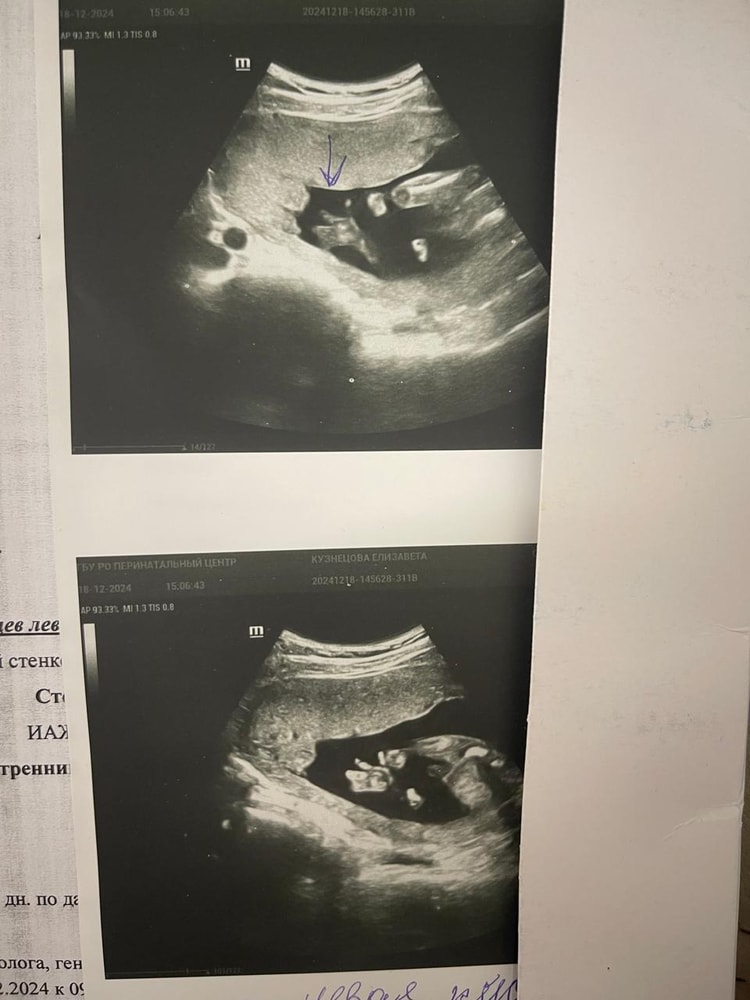

Tatiana, вот где пальцы одной длины, это в Ставрополе делали на экспертнике, остальное Ростов, вот такие диагнозы мне ставили фото где все слиплось это в ПЦ смотрели, когда синдактилию поставили Последнее фото, узи за очень дорого в Ростове Я думаю, что давать оценку как видит врач не стоит, но в данном случае, я очень рада, что супер модный эксперт и спец в своем деле ошибся Изображение Изображение Изображение

Лиза , Изображение